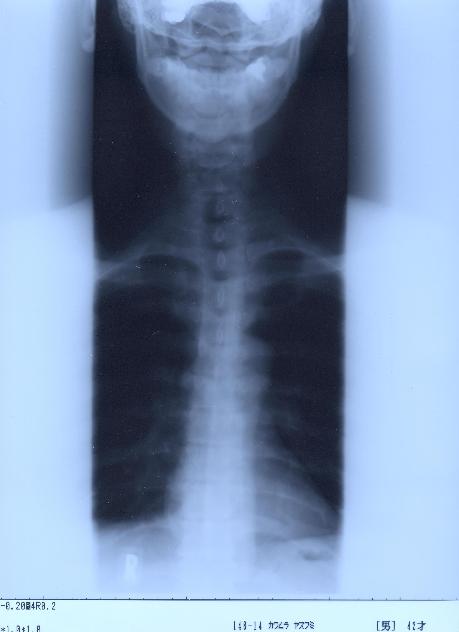

@@Ž„‚Μ”wœ‚Μ‚wόŽΚ^‚Ε‚·@@˜‚ͺ’Ι‚­‚Δ’Ι‚­‚āII@2002/1/22ŽB‰e

‚SDŽρ‚̐³–ʁ@@Šg‘ε